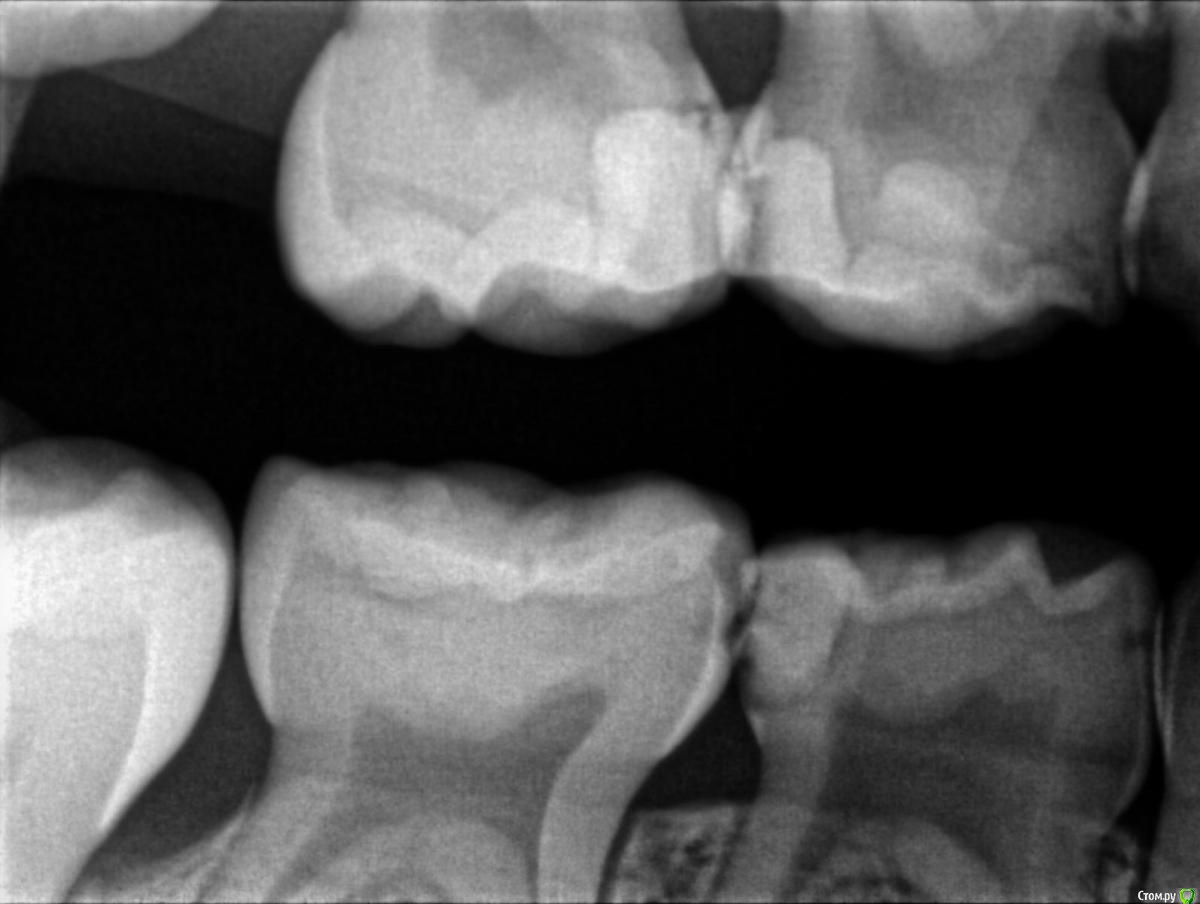

Пошли к врачу, сделали рентген и на рентгене видно что начал образовываться кариес почти на всех молярах, либо под пломбами, либо на стыке зубов. Так как зубы уже леченые доктор говорит что лечить дальше смысла нет, пломба держаться не будет, выпадет снова, предлагают ставить коронки сразу на все моляры, а зуб где уже большая пломба (зуб I на ренгене) просто удалить (не болит) и поставить space mantainer + удалить зуб А.

На наш НЕпрофессиональный взгляд, пломбы не такие уж большие чтоб закатывать в коронки, у старшего сына была аналогичная вообщем то ситуация и когда были в россии да, пломбы вываливались, на их место ставили новые, иногда удаляли нерв, но в итоге до смены зубов все дошло без удаления.

На всякий случае прикрепляю снимки, буду рад услышать мнение.